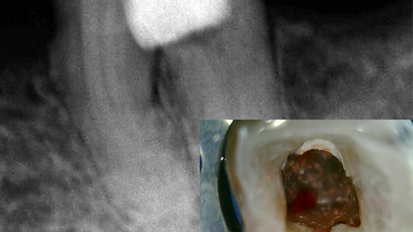

Detección y extracción de diente supernumerario

El autor utilizó el sistema panorámico Hyperion X9 para detectar la posición exacta de un diente paramolar en el maxilar superior y ...